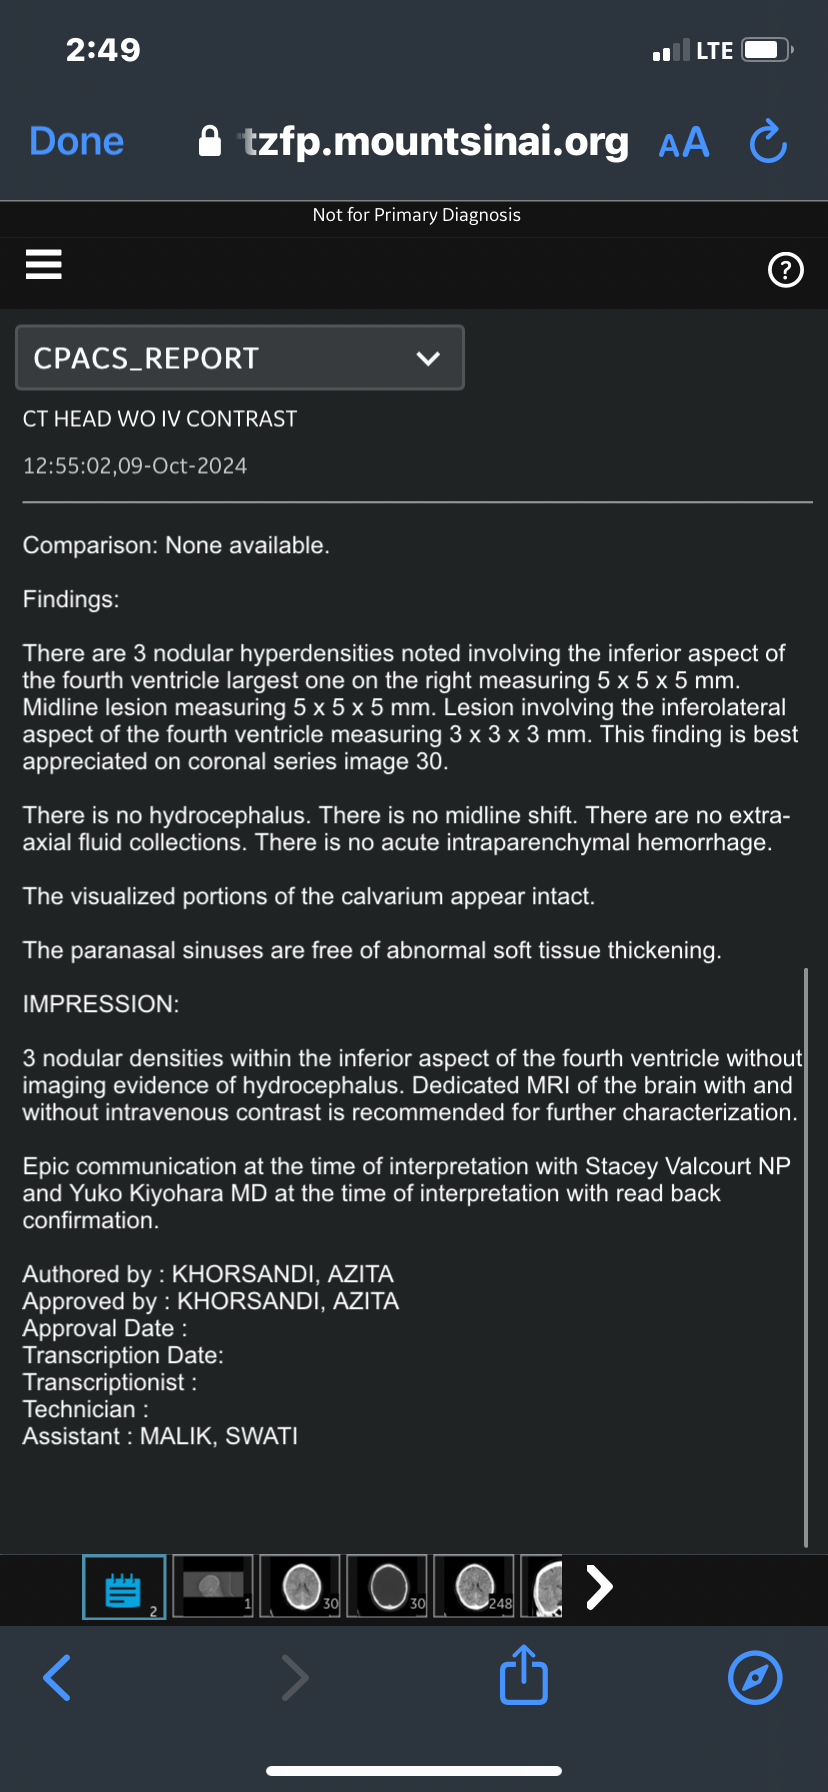

In December, I underwent emergency surgery. Doctors found a large growth in my uterus that was crushing my right kidney. They believe exposure to toxic materials in these illegal units may have contributed to the rapid growth. I was also diagnosed with three brain lesions on the right side of my brain, likely linked to exposure to corrosive gasses used improperly by a previous landlord.